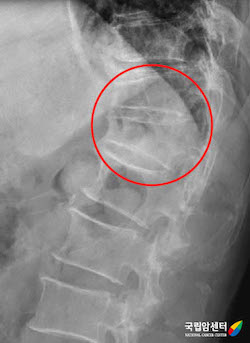

[ 다발골수종 환자에서 발생한 척추뼈의 압박 골절(X ray) ]

다발골수종은 환자들마다 증상의 차이가 있으나 가장 흔한 대표적인 증상으로는 빈혈, 뼈 통증, 신장 수치 상승, 및 고칼슘 혈증이 있습니다. 빈혈은 다발골수종의 원인이 되는 형질세포의 골수 내 증식에 의하며 이로 인한 피로감, 어지러움 및 호흡 곤란 등의 증상이 발생할 수 있습니다. 뼈의 통증 및 골절 역시 다발골수종의 가장 흔한 증상 중의 하나이며 특히 척추뼈의 압박 골절이 발생하는 경우 허리 통증 외에도 하지 마비 등의 신경학적 증상이 동반될 수 있습니다. 고칼슘 혈증으로 인한 구역감, 변비, 의식 및 정서 상태의 변화가 유발될 수 있으며, 신장 기능 저하로 인한 혈액 검사상 신장 수치의 상승 및 단백뇨가 발생할 수 있습니다. 또한 면역 기능의 저하로 인한 감염 증상 및 응고 인자 기능 저하로 인한 출혈 증상도 다발골수종에서 보일 수 있는 증상에 속합니다.

다발골수종은 주로 골수에서 발생하는 혈액암의 일종이나 간혹 골수를 둘러싸고 있는 뼈나 기타 여러 장기에서 고형 종양의 형태를 보이는 형질세포종으로 발생하기도 합니다. 특히 뼈에 침범하는 경우가 흔하며 이러한 경우 척추의 통증이나 압박골절 및 이로 인한 하지마비와 같은 신경학적 증상을 유발할 수 있습니다.

다발골수종은 환자들마다 증상의 차이가 있으나 가장 흔한 대표적인 증상으로는 빈혈, 뼈 통증, 신장 수치 상승 및 고칼슘 혈증이 있습니다. 빈혈은 다발골수종의 원인이 되는 형질세포의 골수 내 증식에 의하며 이로 인한 피로감, 어지러움 및 호흡 곤란 등의 증상이 발생할 수 있습니다. 뼈의 통증 및 골절 역시 다발골수종의 가장 흔한 증상 중의 하나이며 특히 척추뼈의 압박 골절이 발생하는 경우 허리 통증 외에도 하지 마비 등의 신경학적 증상이 동반될 수 있습니다. 고칼슘 혈증으로 인한 구역감, 변비, 의식 및 정서 상태의 변화가 유발될 수 있으며, 신장 기능 저하로 인한 혈액 검사상 신장 수치의 상승 및 단백뇨가 발생할 수 있습니다. 또한 면역 기능의 저하로 인한 감염 증상 및 응고 인자 기능 저하로 인한 출혈 증상도 다발골수종에서 보일 수 있는 증상에 속합니다.